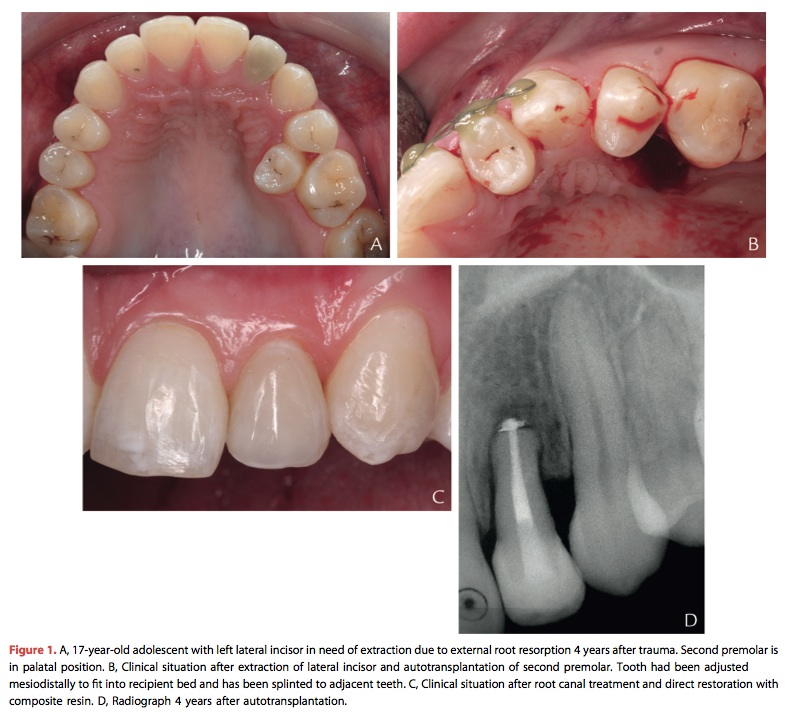

青少年時期缺失前牙的治療方式—Zitzmann(2015)

JPD 2015 Vol.113-1在青少年時期缺失了前牙, 尤其是上顎前牙的缺失會造成功能以及心理的問題. 年輕的女性以及有hyperdivergent growth pattern的患者更要等到確定生長穩定後才能夠去做單顆植牙. 這篇文章的優點是講表格整理的很清楚.

所以一般來說先要看年紀, 能夠自體移植者或矯正關空間最好, 真不行就用resin-bonded等植牙